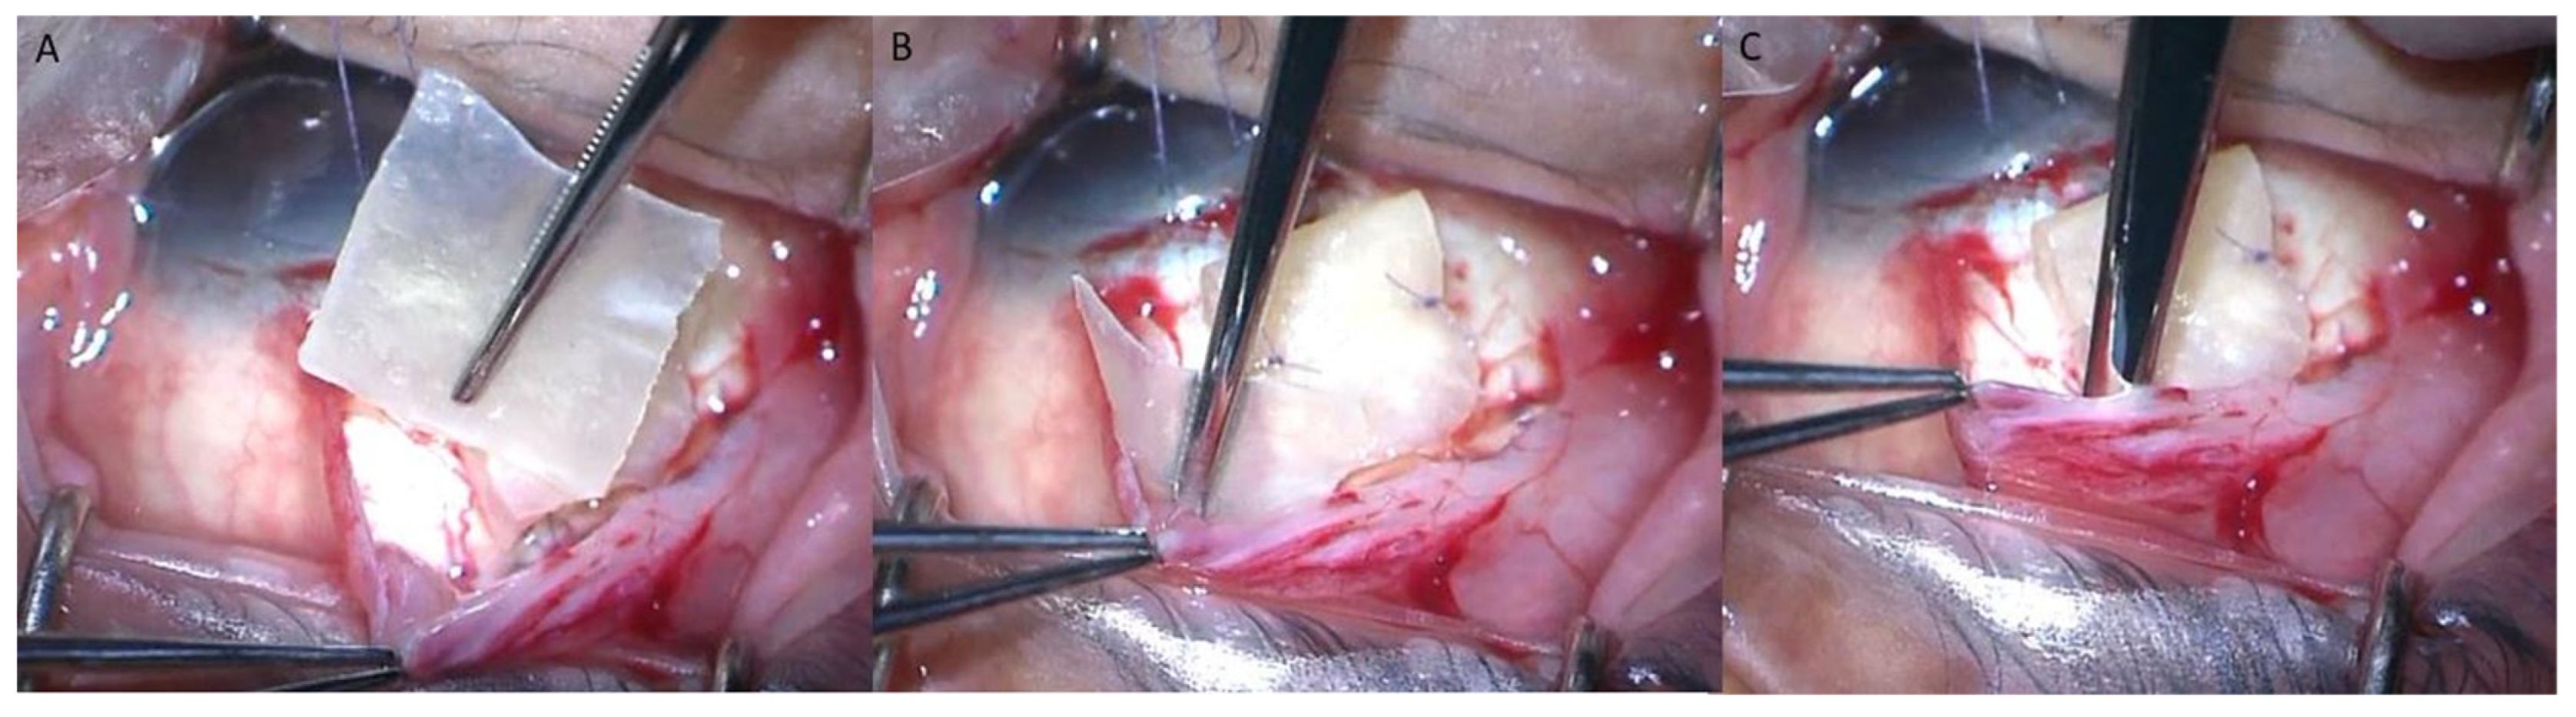

The AGV implantation surgery was performed by two glaucoma specialists (C.K.P. and K.I.J.) using the Ahmed glaucoma valves Model FP7 (New World Medical, Ranch Cucamonga, CA, USA). The AGV implantation was performed using a standard surgical technique. A fornix-based incision was made through the conjunctiva and Tenon’s capsule in the superior temporal quadrant, while radial-relaxing incisions were made on one side of the conjunctival flap to improve surgical exposure. After the valve was primed with a balanced salt solution, the endplate was inserted in the sub-Tenon’s space located 8 mm posterior to the corneoscleral limbus and secured to the sclera with absorbable sutures. A track was made 1–2 mm posterior to the corneoscleral limbus to insert the tube into the anterior chamber with a 1 mm knife. A viscoelastic solution was injected into the anterior chamber using a 23-gauge needle. Subsequently, the tube was cut and inserted into the anterior chamber and secured to the sclera using 8-0 Vicryl sutures (Johnson & Johnson, New Brunswick, NJ, USA). Partial ligation of the tube was performed with a releasable suture using 8-0 Vicryl to reduce the rate of early postoperative hypotony. The extraocular portion of the tube was covered with two layers of 4 × 4 mm pericardium allograft (Maxxeus, Kettering, OH, USA), which was an 8 × 4 mm pericardium patch folded in half. An additional step was performed in the with-expansion group by inserting an 8 × 6 mm pericardium graft adjacent to the AGV body at the sub-Tenon’s space (Figure 1). The conjunctiva was approximated and sutured using 8-0 Vicryl sutures. Topical antibiotics and steroids were administered following the surgery. The releasable suture was removed at 1 week post-surgery when there was no sign of hypotony. The only surgical step that was different between the groups was the insertion of the additional 8 × 6 mm pericardium graft adjacent to the AGV body; all the other steps in the surgery were identical between the two groups.

Figure 1. Intraoperative procedures on a right eye; additional pericardium graft inserted adjacent to the Ahmed glaucoma valve (AGV) body, implanted at the superotemporal quadrant. (A) The additional pericardium graft sized 8 mm × 6 mm. (B,C) Pericardium graft was inserted in the sub-Tenon’s space adjacent to the AGV body.